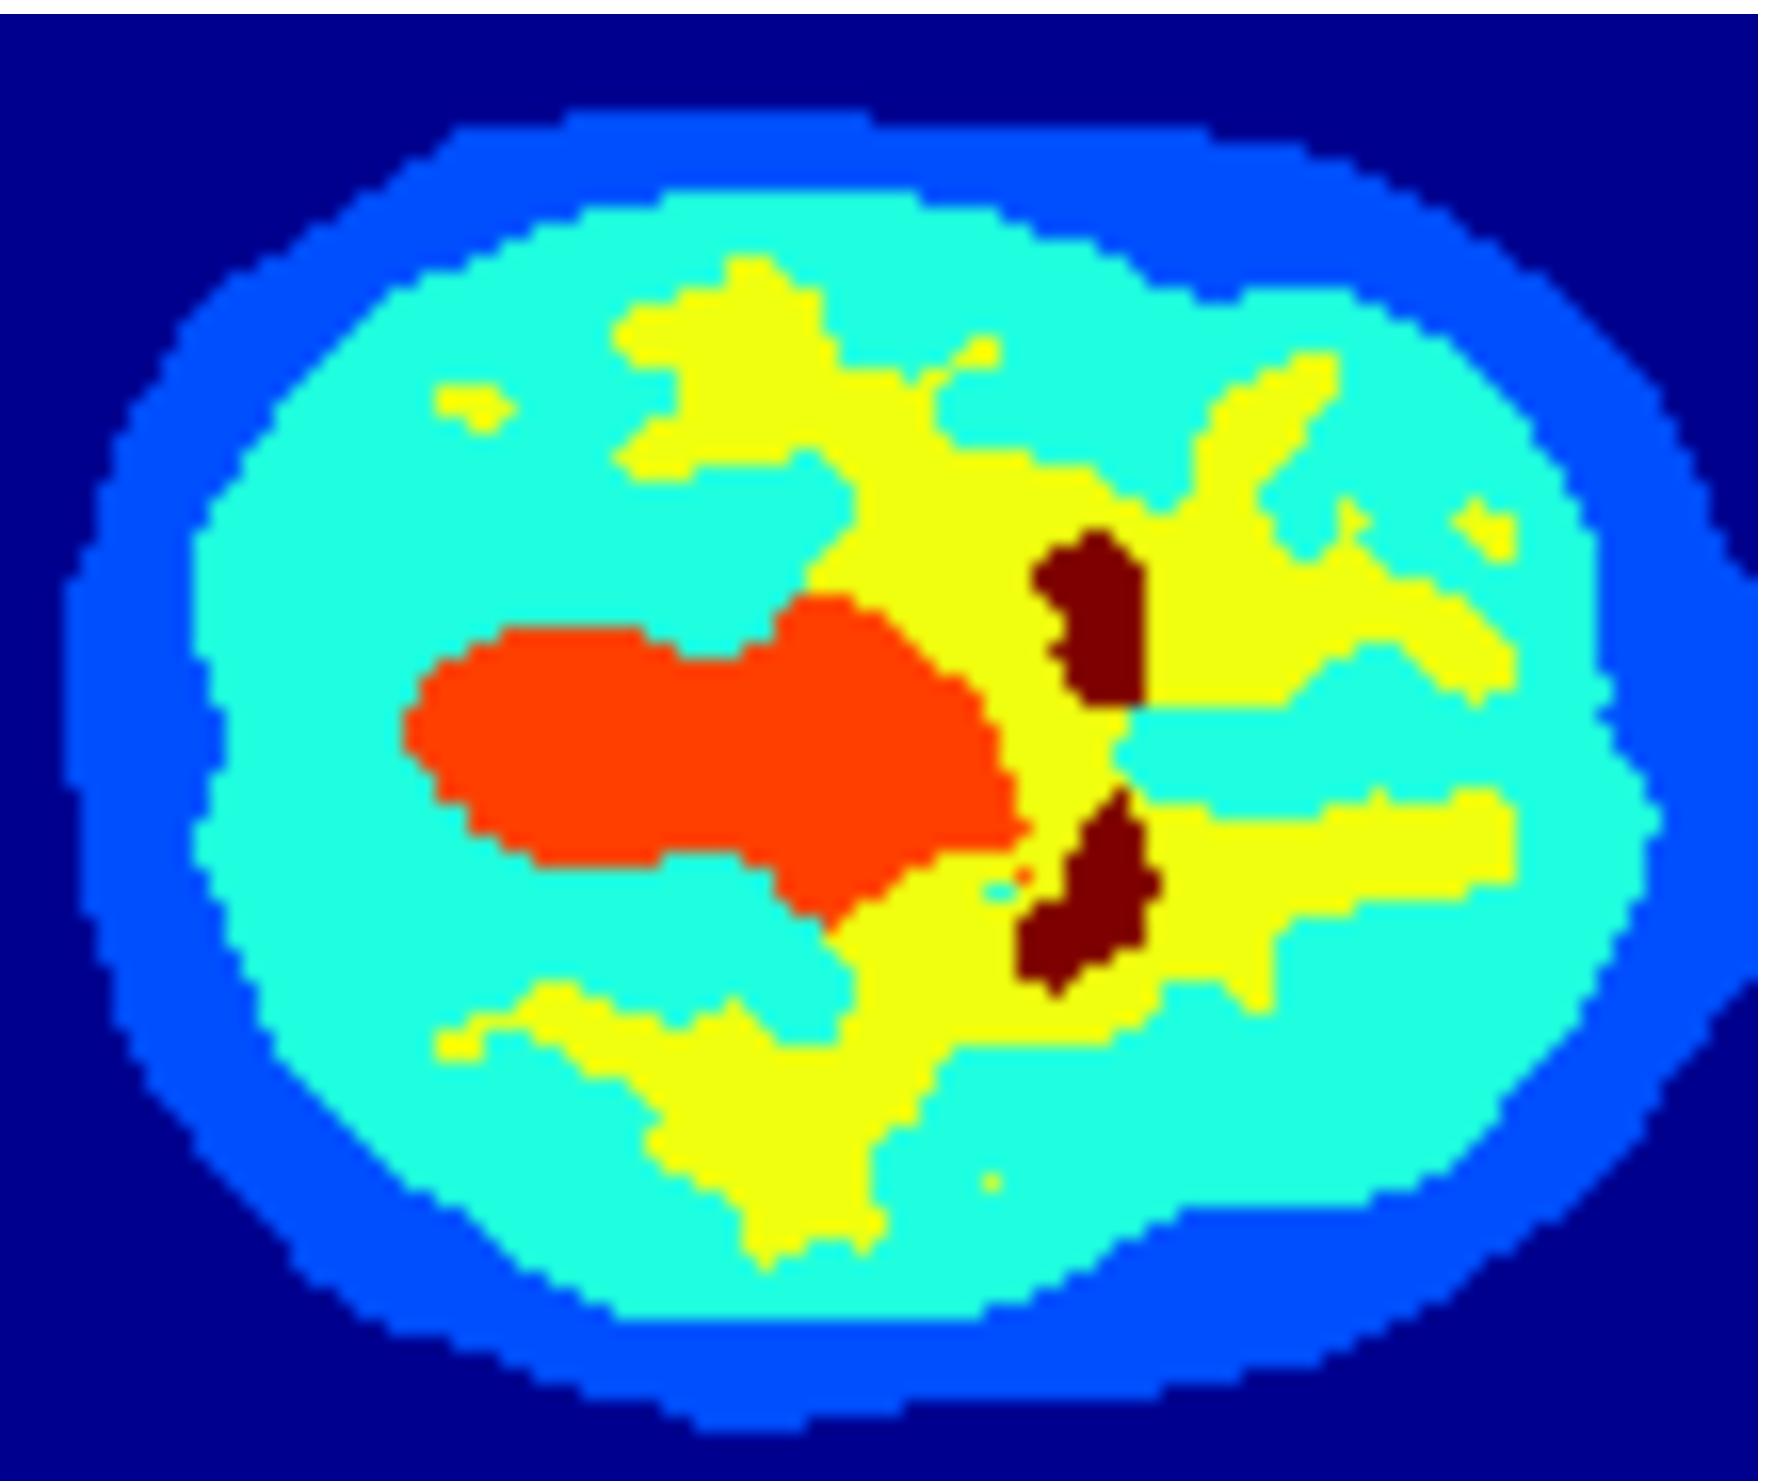

Saad et al. [32] use a kinetic model to devise a multi-class, seed-initialized, iterative segmentation algorithm for molecular image quantification. Due to the low signal-to-noise ratio and partial volume effect present in dynamic-positron emission tomography (d-PET) data, their segmentation method has to incorporate prior knowledge. In this noisy setting, the segmentation of a basic random walker [14] would just result in Voronoi regions around the seed points. A new extension by Saad et al. makes this method usable for noisy data by adding energy terms that account for desirable criteria, such as data fidelity, shape prior, intensity prior, and regularization. In order to attain the superior segmentation quality of the algorithm, a proper choice of weights for the energy mixture is crucial.

To facilitate this choice of weight parameters, their code also provides numerical performance measures that assess the quality of each class. One such measure is the Dice coefficient [9], which gives a ratio of overlap with labelled training data. A second measure expresses an error of the quality of the kinetic modelling. Overall, the algorithm is influenced by factors or parameters. Ten response variables provide the quality measures per class, disregarding background.

Theoretically, the parameter calibration could proceed by numerical optimization of the performance with respect to the weights of the energy terms. However, for instance the Dice coefficients that indicate agreement of the segmented shape with given training data for putamen, using the two configurations of Figure 1(c) and (d), are both above the 90th percentile of the sampled configurations and less than standard deviations apart. Numerically, this means that both segmentations are of the same, near optimal quality. Yet by visual inspection, it is possible to tell that the putamen (PN) shape in (d) is favourable over the one obtained in (c). Hence, guidance of a human domain expert is desirable to visually sort among several candidate solutions in order to find an improved segmentation, which is hard or impossible to choose automatically. An interactive workflow that facilitates such a procedure is subject of Section 5.2.